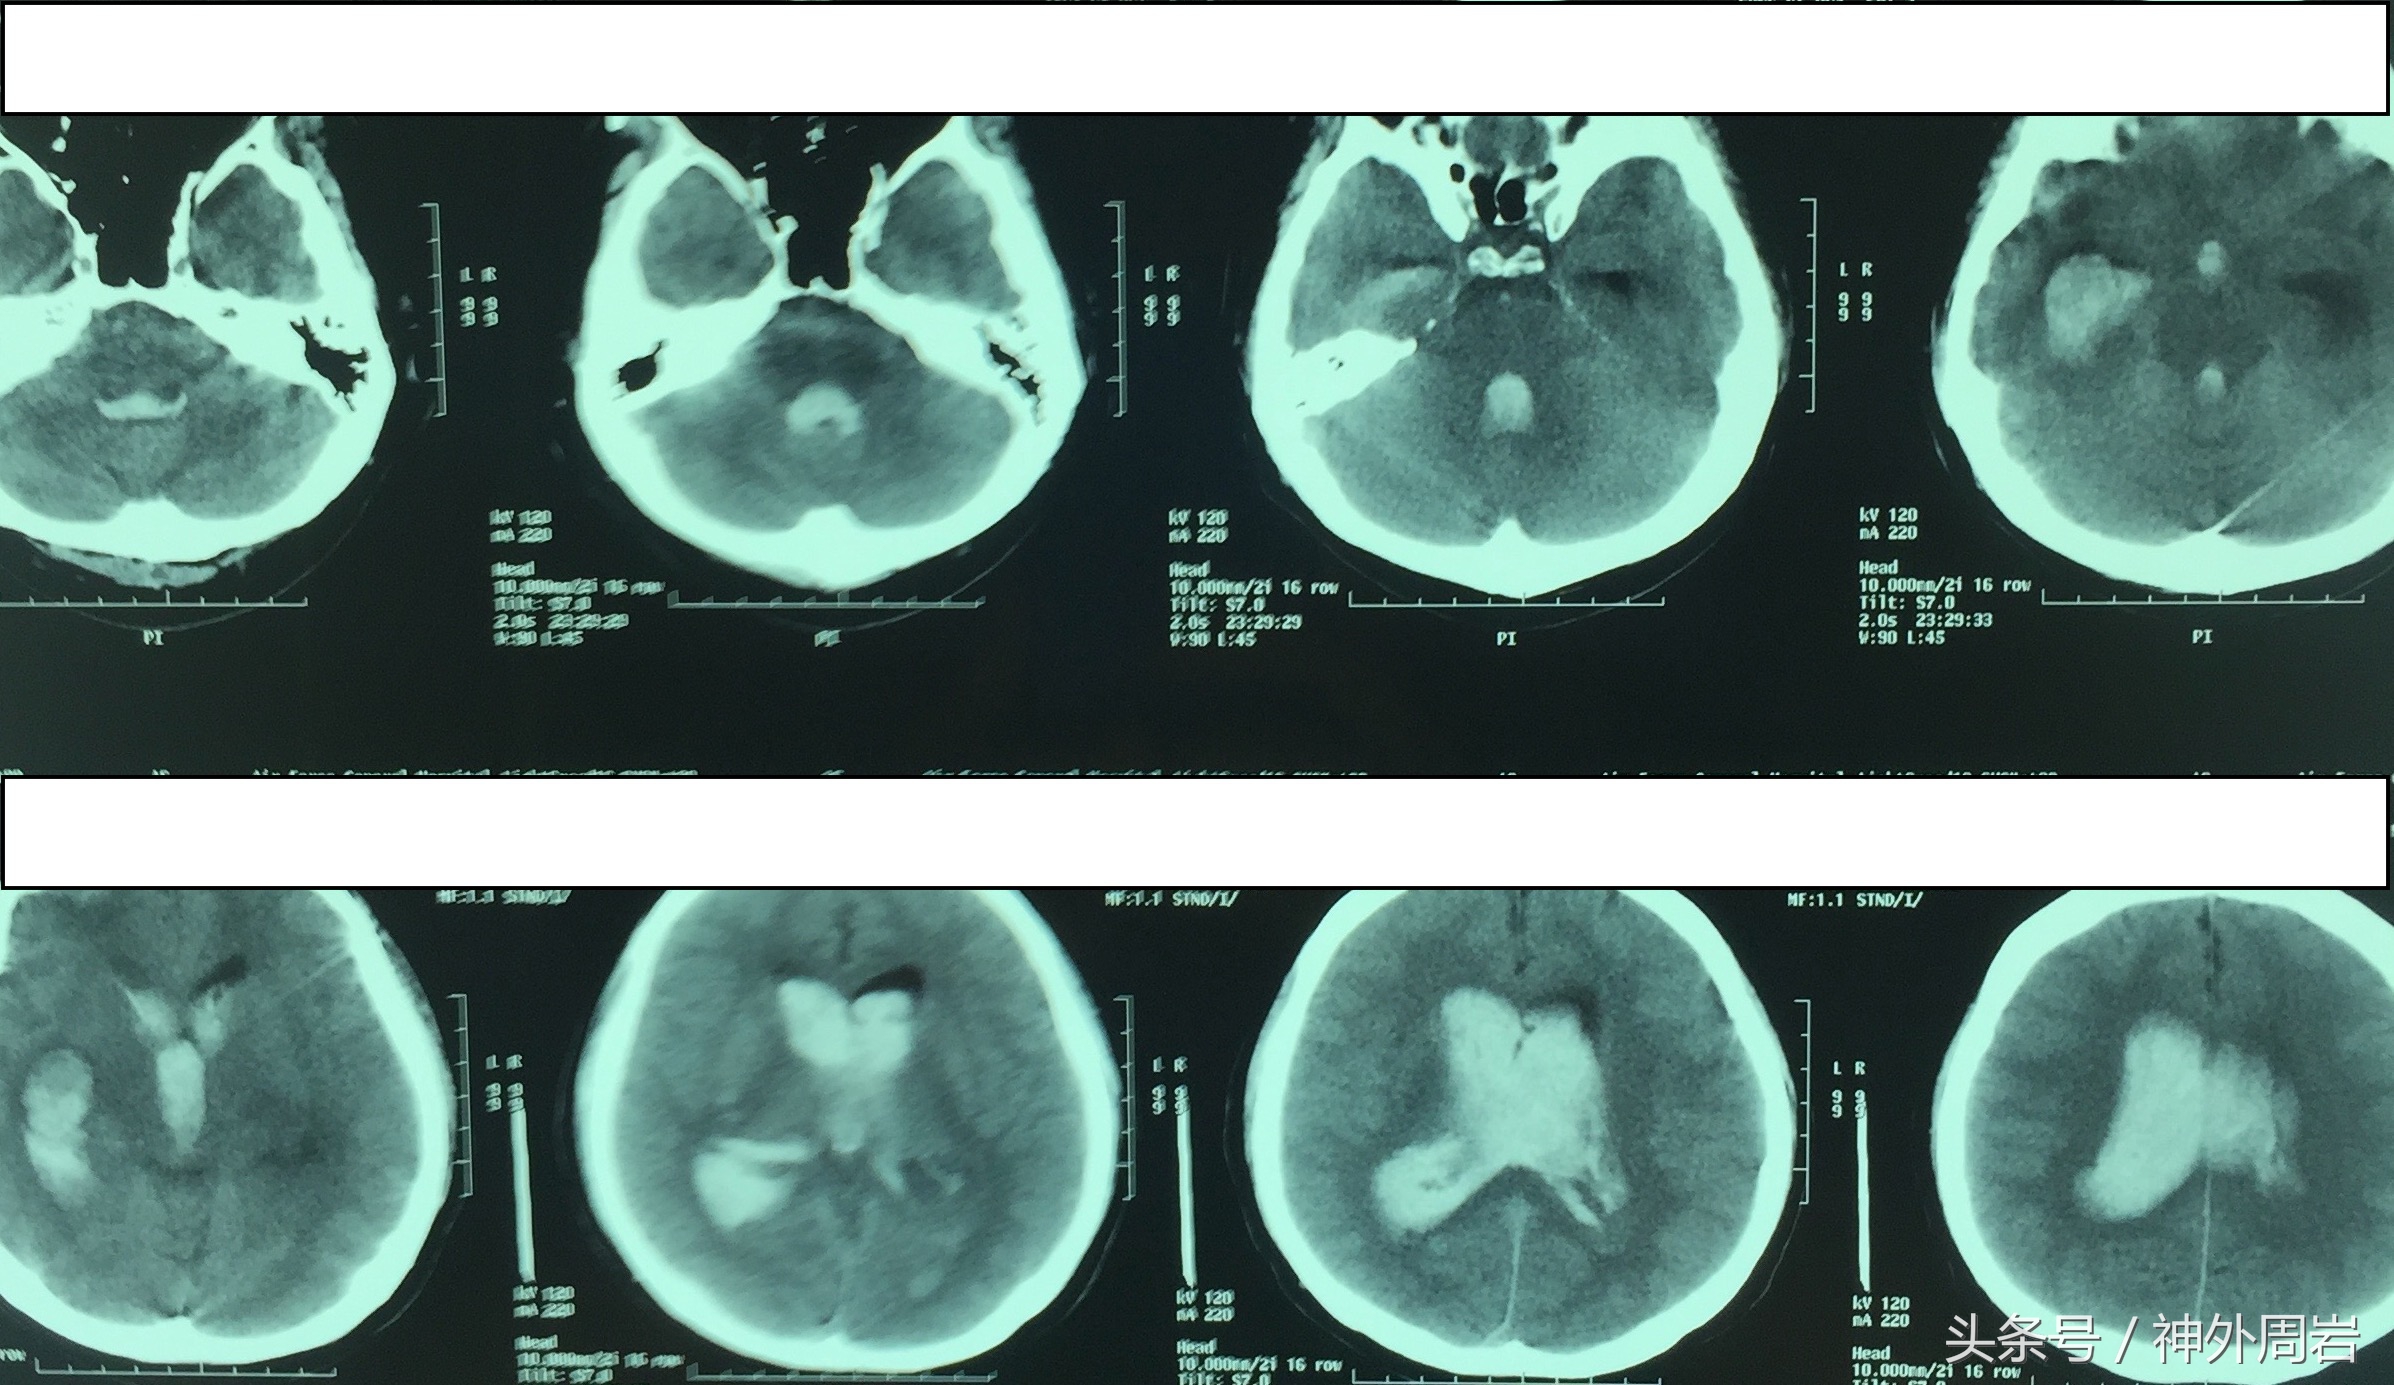

晚上22点,55岁的老宫正在沙发上休息,突然出现了极为剧烈的头痛,随即进入意识模糊状态,伴有四肢无力。在紧急送往医院过程中,呕吐2次,呈喷射样,意识障碍程度逐渐加深。紧急脑CT检查发现脑室系统充满了血。

诊断:自发性脑室出血

当血液完全灌满整个脑室系统时,我们称之为“铸型”。

自发性脑室出血虽然发生率不高,但是一种预后凶险、并发症多、病死率高的严重疾病。严重者出血后即可进入昏迷,数小时内死亡。

老宫就是典型的出血性烟雾病引起的自发性脑室出血!